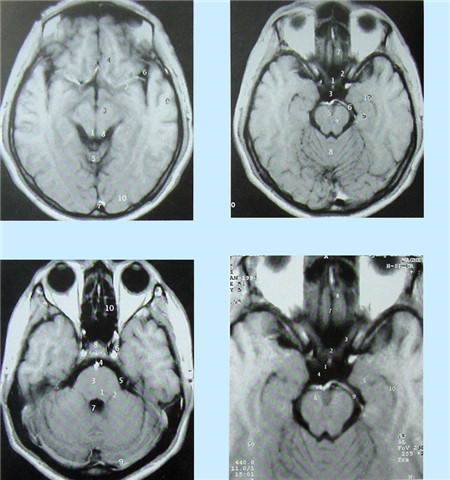

核磁共振成像無電離,對機體沒有不良影響。MRI對檢測腦內(nèi)血腫、腦外血腫、腦腫瘤、顱內(nèi)動脈瘤、動靜脈血管畸形、腦缺血、椎管內(nèi)腫瘤、脊髓空洞癥和脊髓積水等顱腦常見疾病很有效。

核磁共振成像設(shè)備價格昂貴,檢查費用也較高,它與CT都可以提供斷層的靜態(tài)掃描圖像。

超聲經(jīng)顱多普勒血流分析儀(TCD)提供的是實時動態(tài)的腦血管的血流動力學(xué)資料。核磁共振血管成像(MRI)提供的是大腦實質(zhì)細胞的損壞與形態(tài)學(xué)上改變的影像學(xué)資料 。數(shù)字減影血管造影(DSA)提供的是腦血管瞬間形態(tài)學(xué)上的變化,且有創(chuàng)傷。

數(shù)字減影血管造影DSA腦血管圖像顯示                                                      核磁共振MRI掃描腦組織圖像